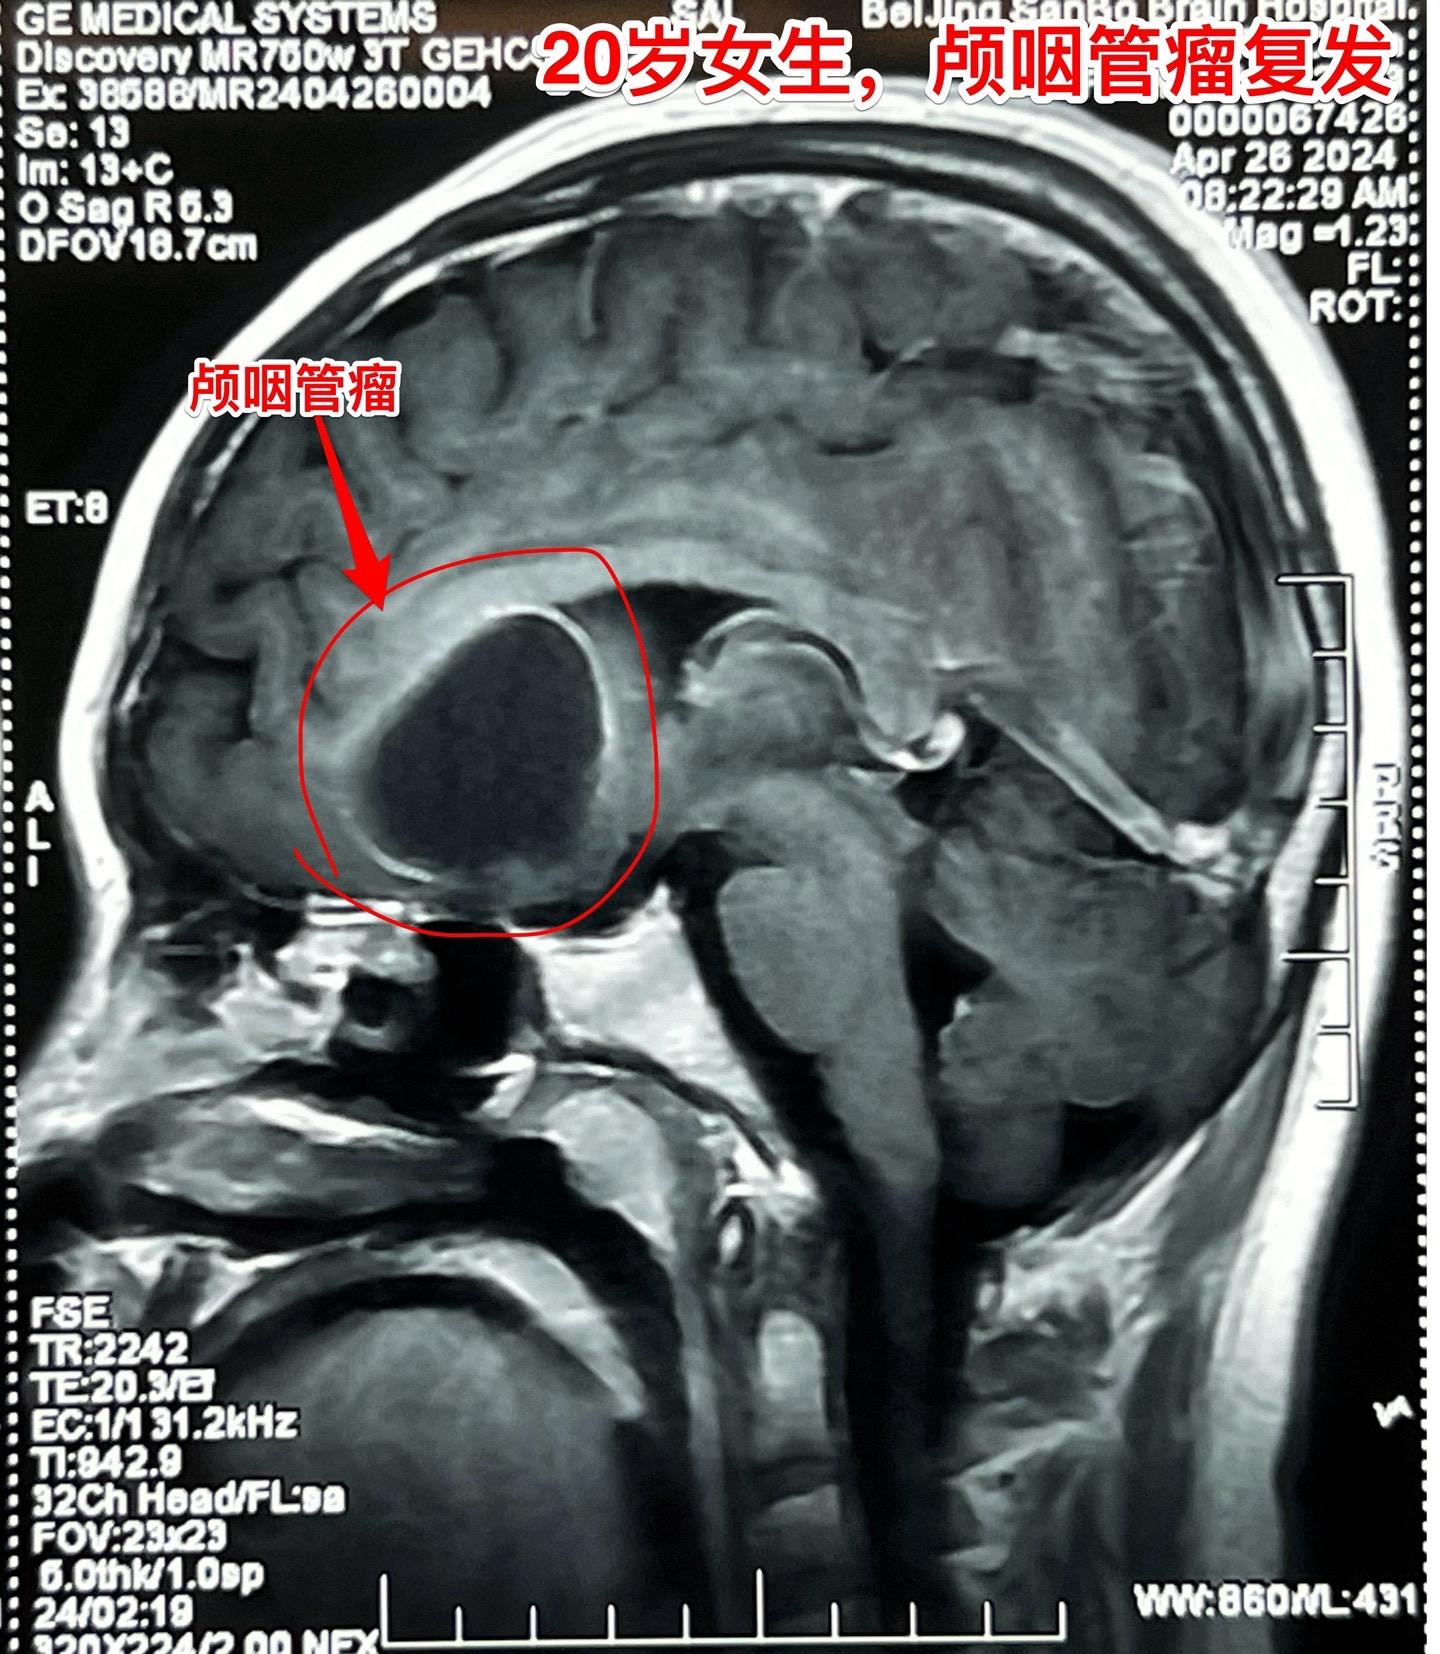

20岁女生,颅咽管瘤两次复发。菏泽女大学生,患颅咽管瘤将近十五年。第一次开颅手术,第二次经鼻手术。病人右眼视力比较差,经过激素替代治疗,看起来还很健康,能上大学正常读书。这次发现两个病灶,一个是囊,嵌入右侧额叶脑实质中;另一个是大钙化,像块石头,长在垂体窝里。这样的复发颅咽管瘤适合开颅手术。

4月30日作了开颅手术,将两块肿瘤均切除了。术前有些担忧脑脊液鼻漏,术后并没有出现。